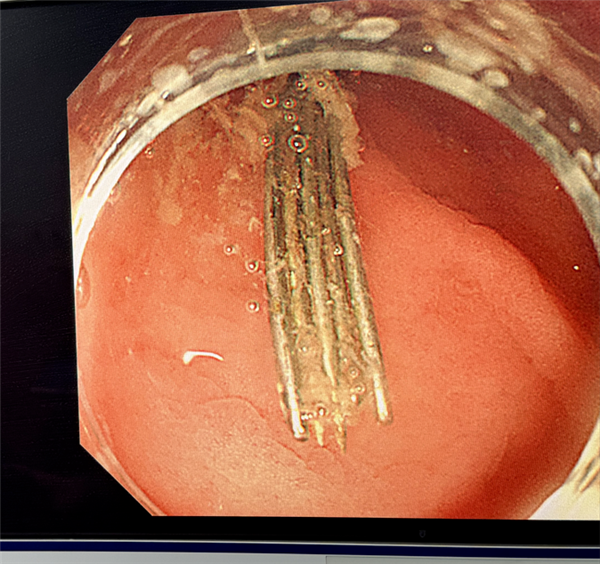

内镜缓缓进入胃腔,屏幕上的画面让人不寒而栗:

好在医生凭借丰富的临床经验和精湛操作,经过三个小时的连续奋战,最终12根长4–5厘米的绣花针被完整、安全地全部取出。